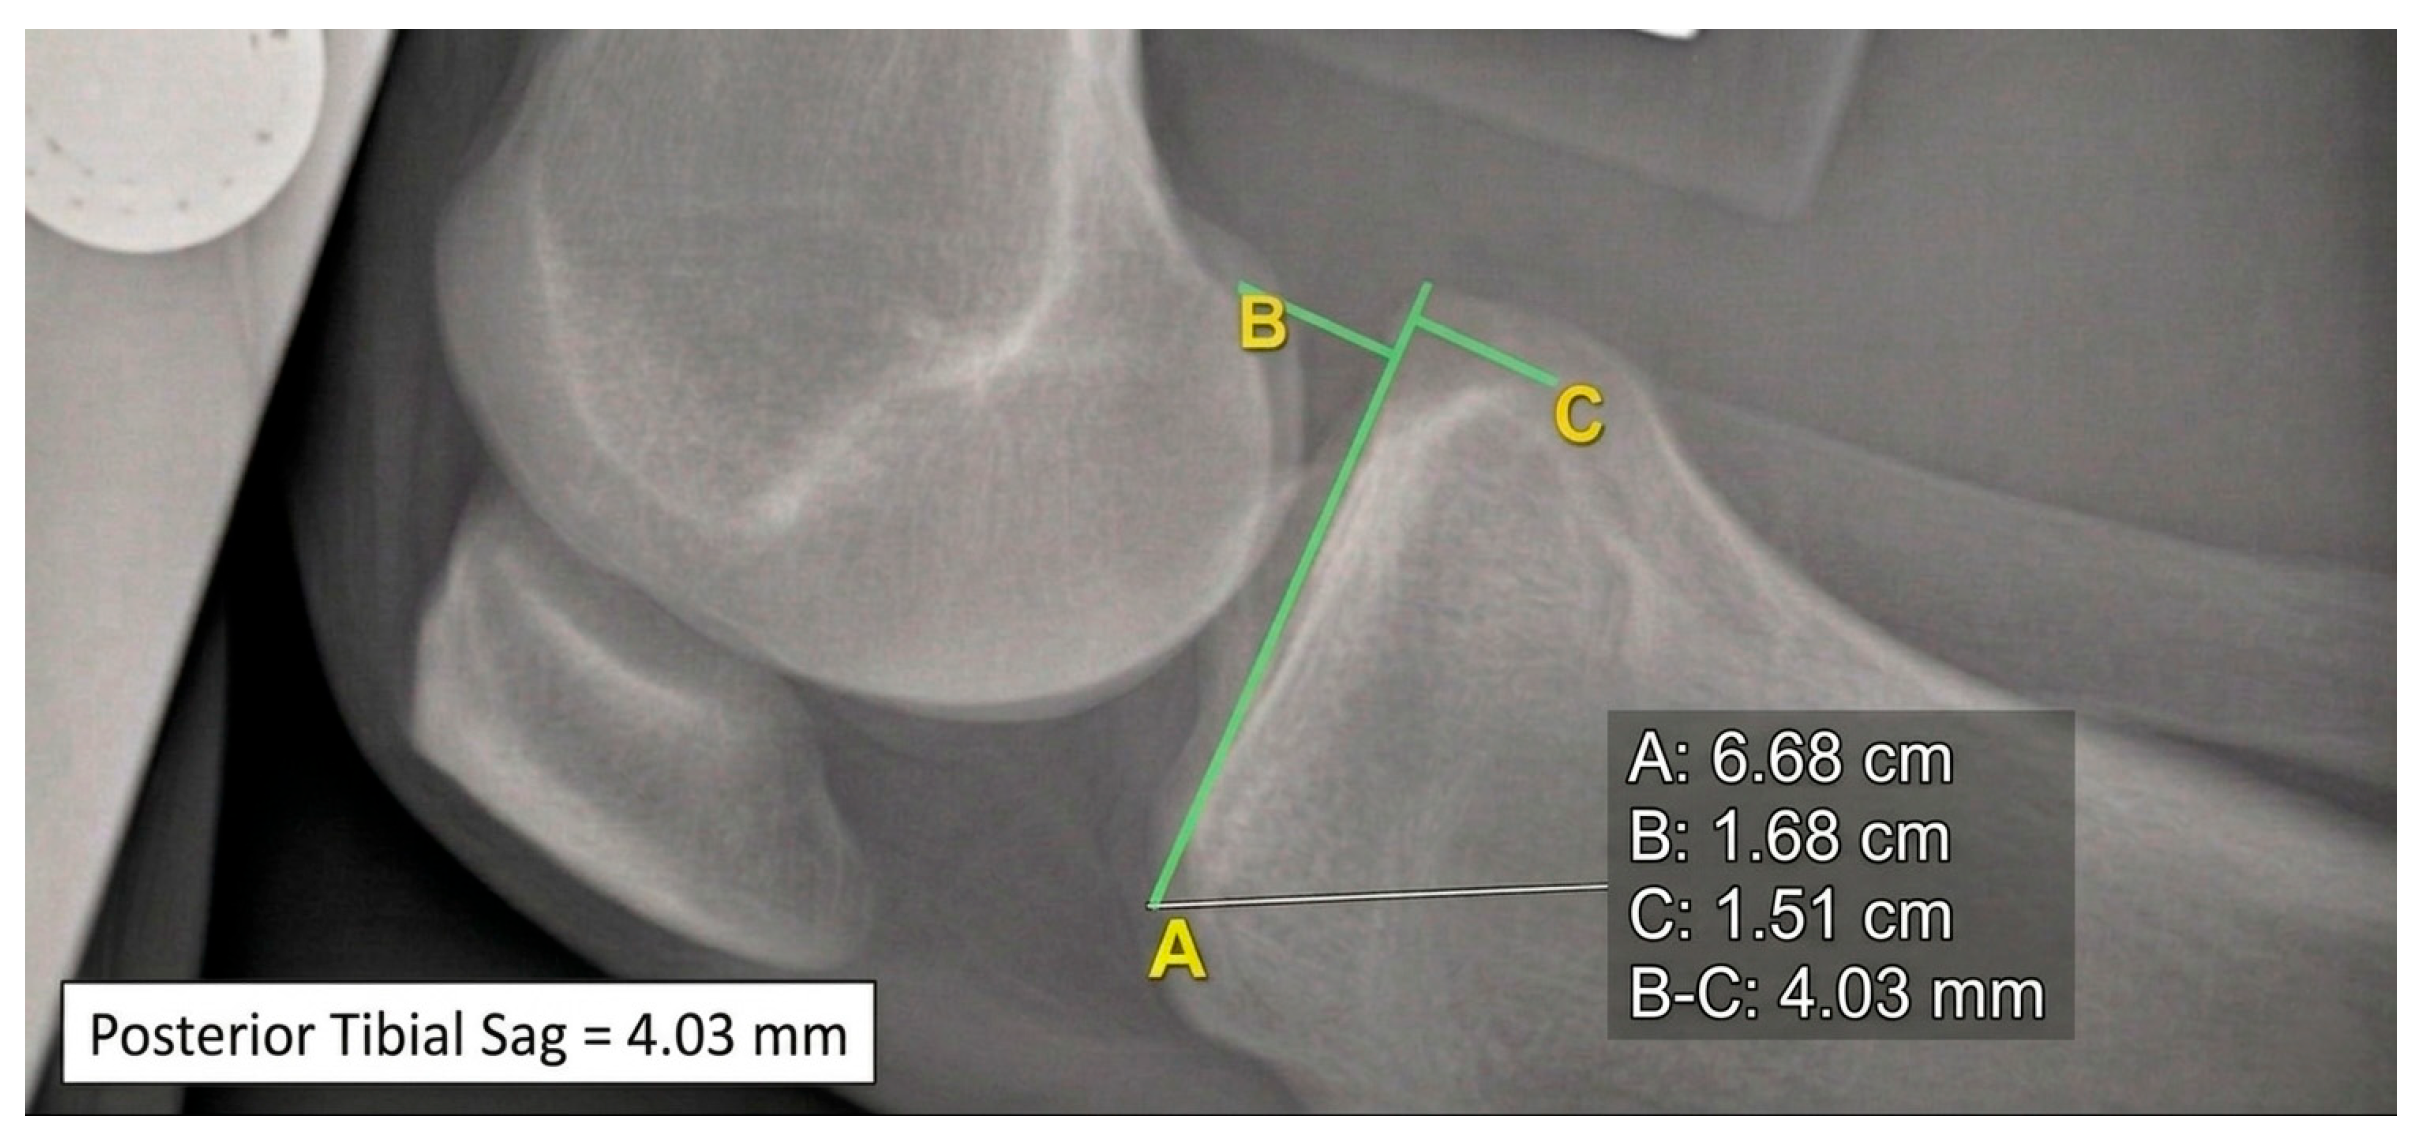

Figure 2. 90° knee flexion without brace and without anterior–posterior tibial stress; posterior tibial translation = 4.03 mm.